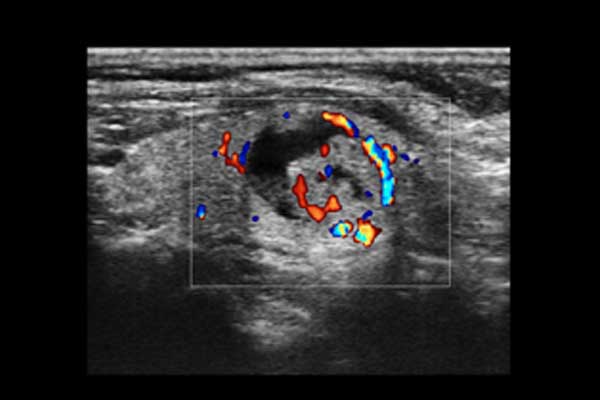

X3便携式彩色多普勒超声诊断系统是一款将小巧机身与卓越性能结合的便携产品。高度集成化的硬件模块,配合时尚前沿的人机工学设计打造了X3,如笔记本电脑般轻薄灵巧的机身、同时也赋予它突破体量限制的优异整机性能。轻便小巧,简单易用。图像清晰,X3可以随时随地满足您的使用需求。

Auto IMT血管内中膜自动测量

X3搭载了丰富的探头群,可全面满足腹部、泌尿系统、浅表器官、妇科、产科、心脏及外周血管等常规领域应用。轻薄灵巧的主机机身、人性化的台车设计、实用的三探头扩展器、使得它无论在超声科还是在移动诊疗应用中都可以轻松应对。